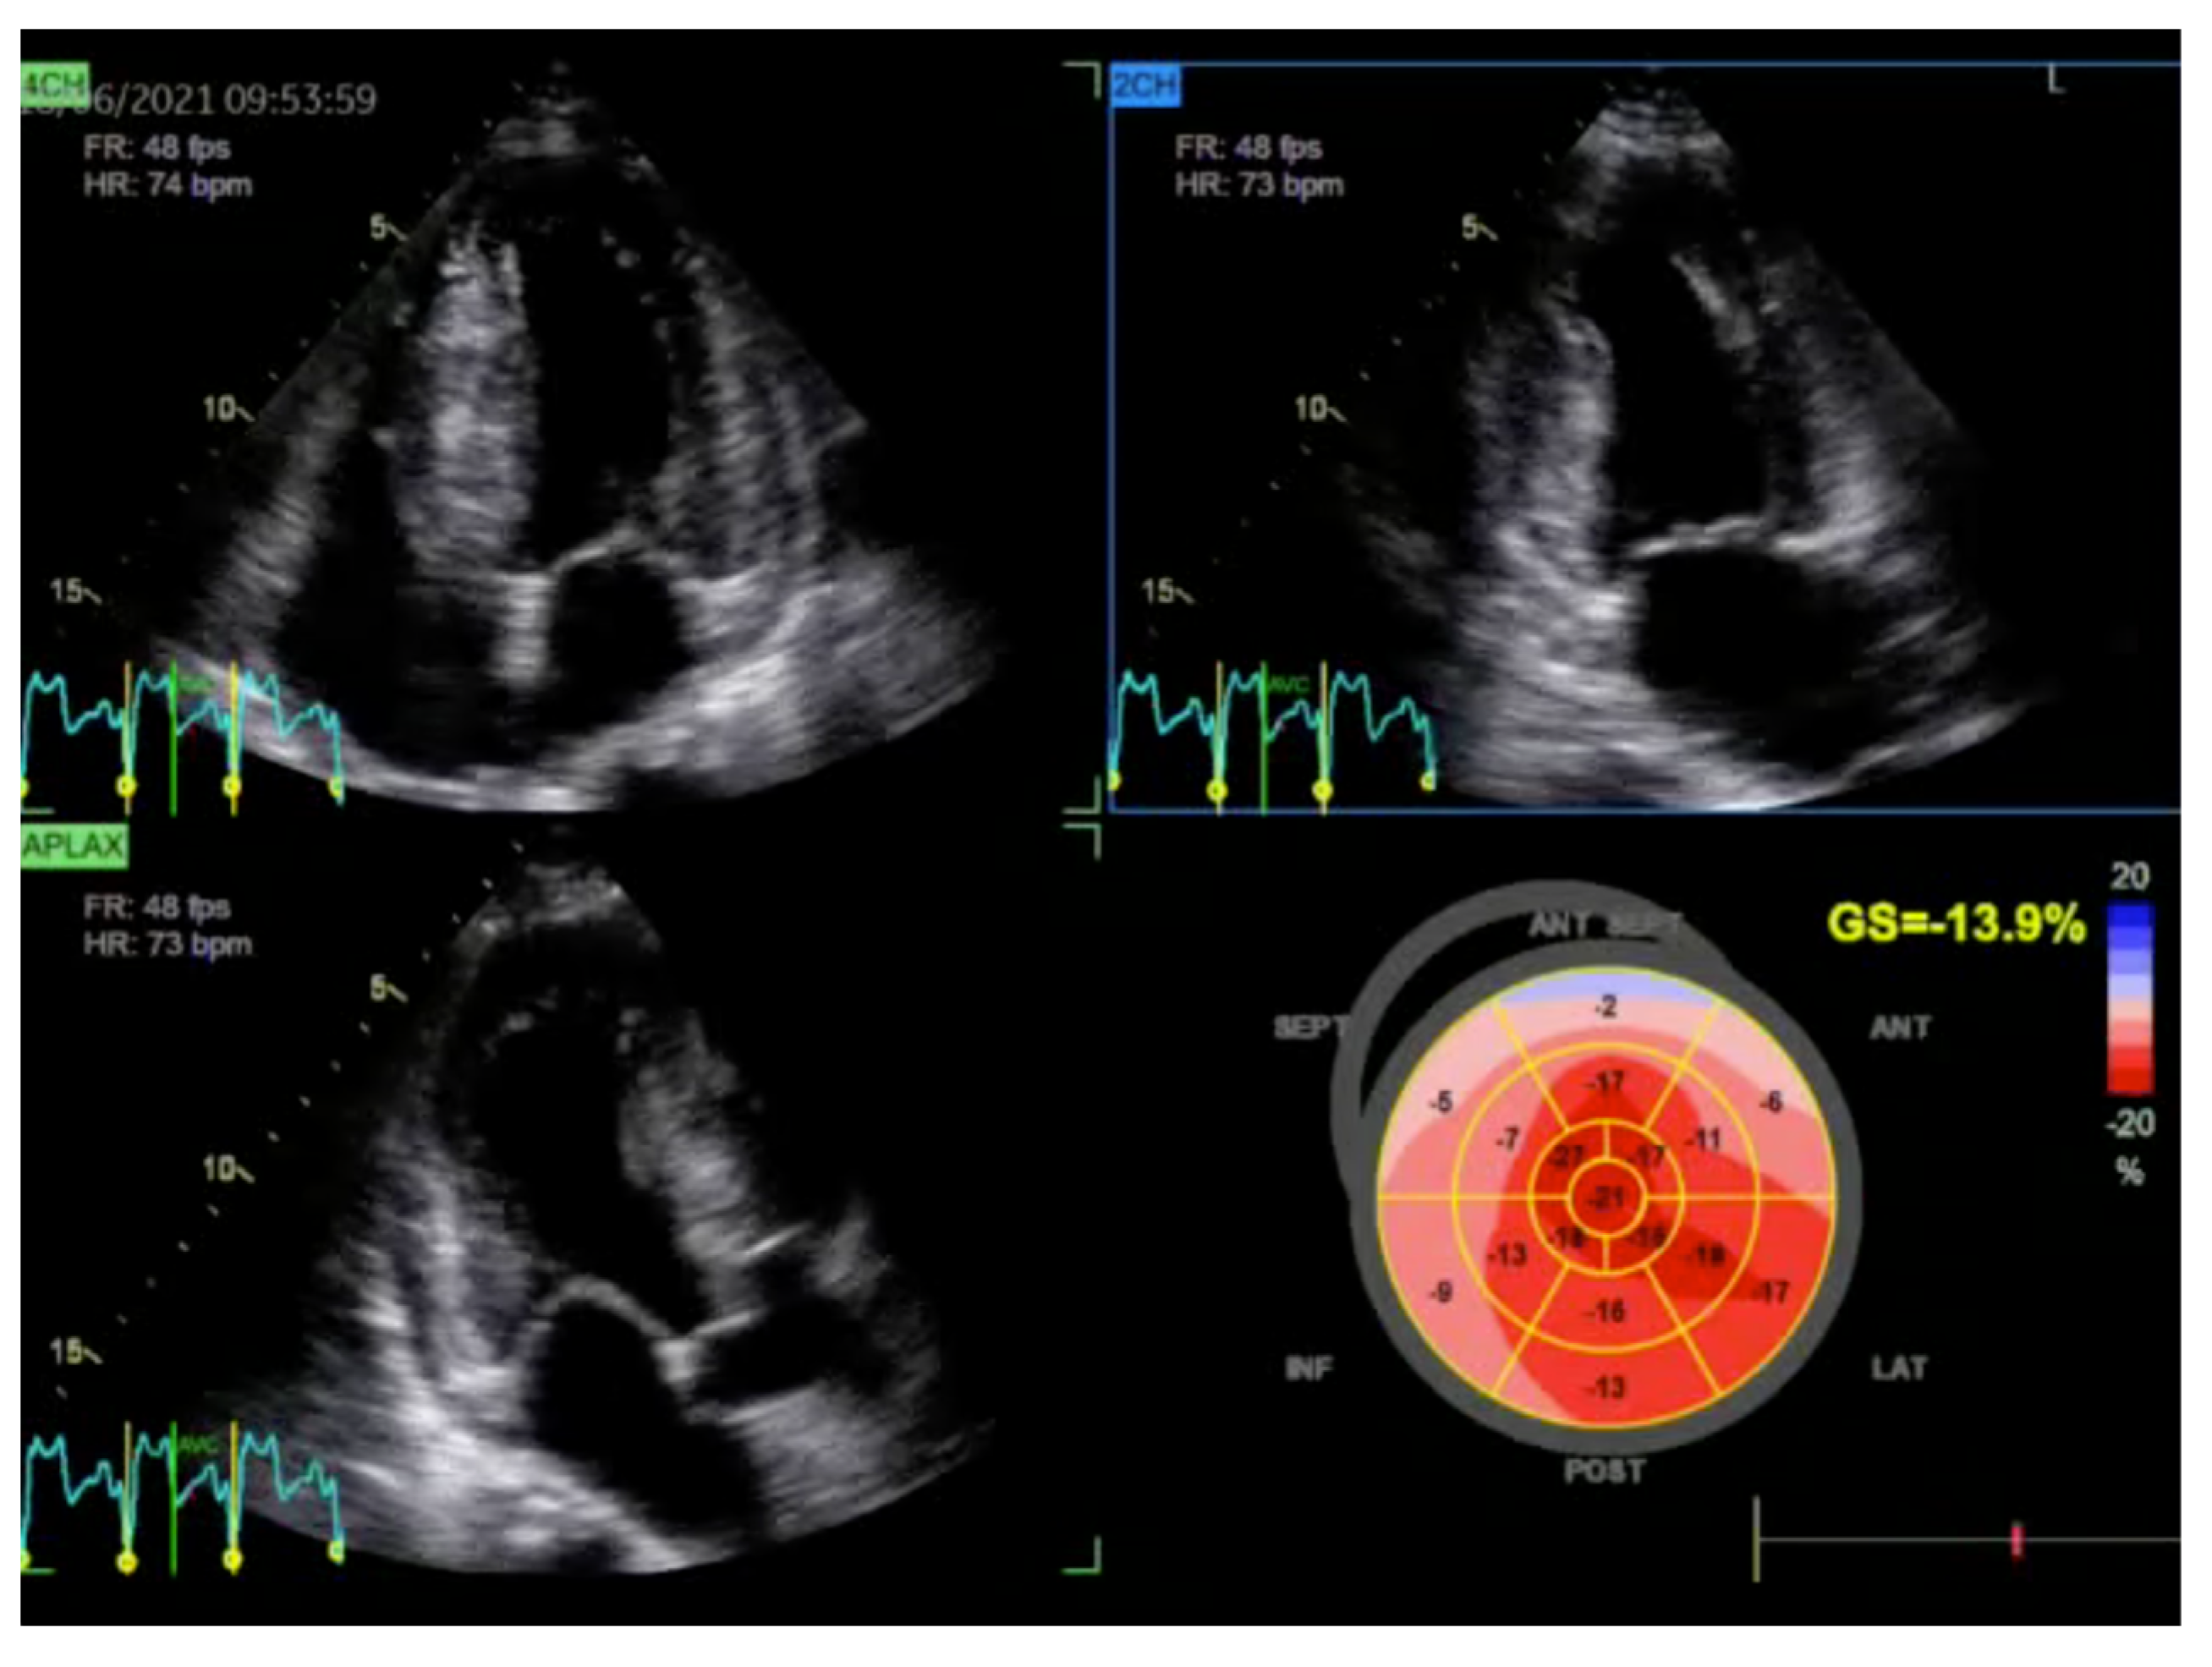

2.1. Echocardiography: The First Line of Diagnosis

- Gherbesi, E.; Gianstefani, S.; Angeli, F.; Ryabenko, K.; Bergamaschi, L.; Armillotta, M.; Guerra, E.; Tuttolomondo, D.; Gaibazzi, N.; Squeri, A.; et al. Myocardial strain of the left ventricle by speckle tracking echocardiography: From physics to clinical practice. Echocardiography 2024, 41, e15753. [Google Scholar] [CrossRef]